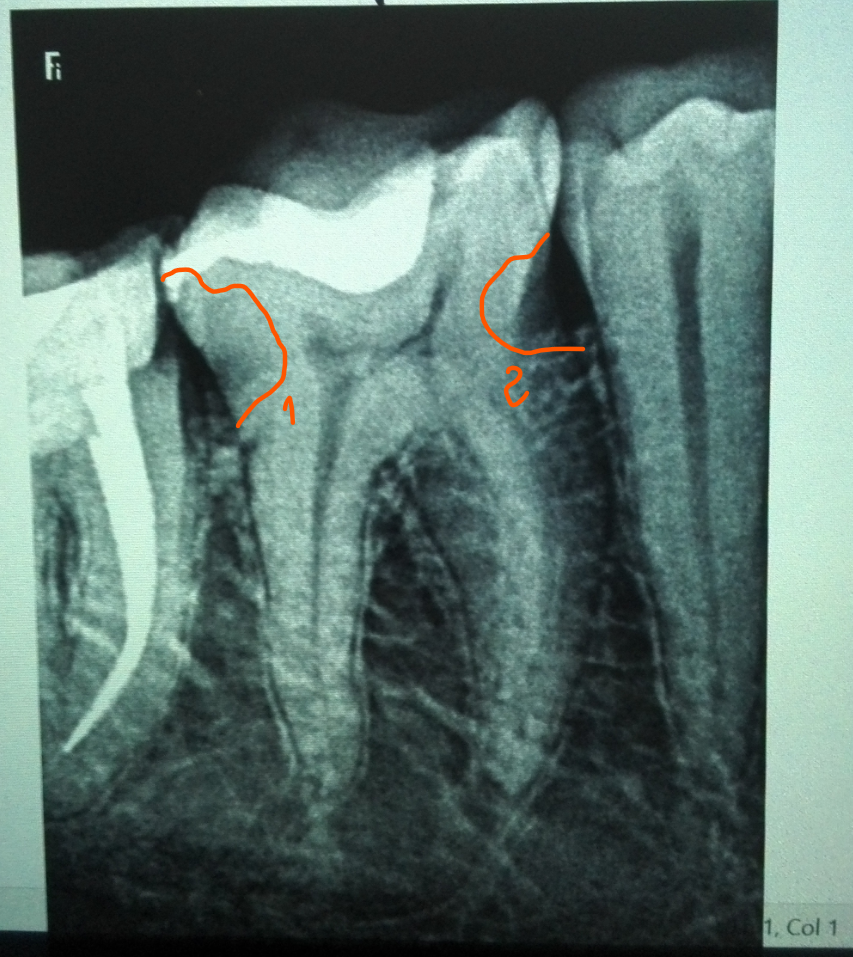

на втором фото, обозначены "подозрительные" места,  похоже ли это на кариес ?

Original-2020-08-20-080751.png

edited-2020-08-20-080751.png